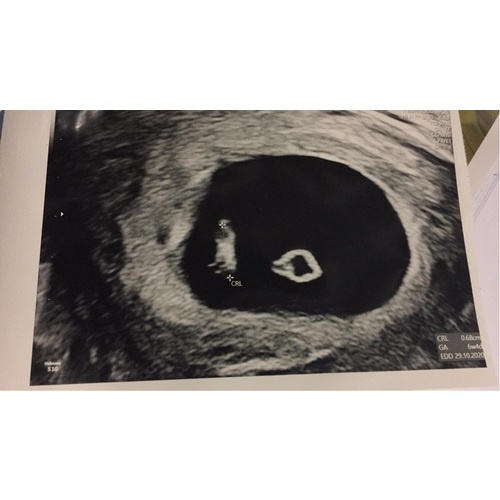

Hieronder de foto van mijn echo toen!

Dus je kan echt al wel wat zien hoor😄

Weet enkel dat het linkse, het kindje is! Was ook het belangrijkste. Had dat ander pas gezien thuis, dus niet gevraagd.

Ik heb al een kloppend hartje gezien toen. Hangt van baby tot baby af blijkbaar. Heb ook al gehoord dat sommige dit nog niet zagen, maar waarbij de zwangerschap ook succesvol was.

Dus zou je daar niet te hard op fixeren.